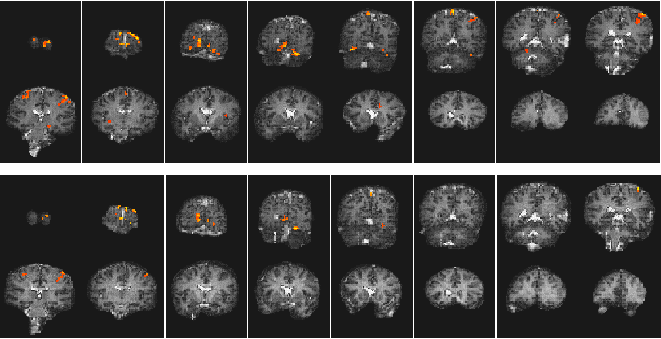

Low distortion EPI images were acquired using a two shot multislice interleaved EPI technique with a matrix size of 128 x 128 and a switching rate of 1.9 kHz. These were compared with images from a single shot experiment with the same matrix size. The activation paradigm consisted of 32 seconds of the subject observing the pattern reversal (4 Hz) of a checkerboard display whilst finger tapping, followed by 32 seconds of rest, repeated eight times. The whole brain, in each experiment, was scanned in 16 slices, in a period of 8 seconds. The images were registered and spatially smoothed (FWHM 4 mm), and correlated to a square wave of the same period and phase as the stimulus. Activation maps were thresholded, using the theory of Gaussian random fields, based on peak height and spatial extent. The activation maps were overlaid on white matter inversion recovery images (TI 1200 ms) acquired using either the single shot or two shot technique.

The resulting images are shown in Figure 5.14. Both methods produced very similar activation maps, with slightly more activation detected in the single shot technique. This is because the shot-to-shot signal to noise was not quite as good in the two shot experiment, presumably due to slight subject movement between interleaves. The level of distortion is slightly less in the two shot case and these results demonstrate the viability of carrying out low distortion interleaved EPI at 3.0 T.

Figure 5.14 Activation images from two experiments both involving a the same visually cues motor task. The top set of images were acquired using single shot EPI, and the bottom set acquired using two shot interleaved EPI.